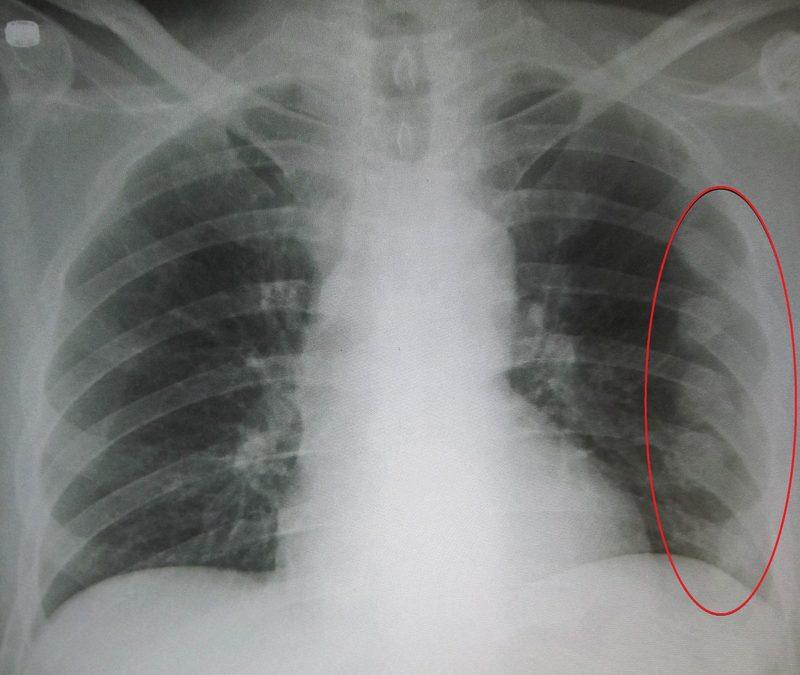

Чтобы определить трещину в ребре, необходимо провести рентгенологическое исследование. На основании снимка специалист выявляет место, где локализуется повреждение. По рентгенологическому фото врач также получает информацию о характере травмы.

Фото снимка при переломе ребер: